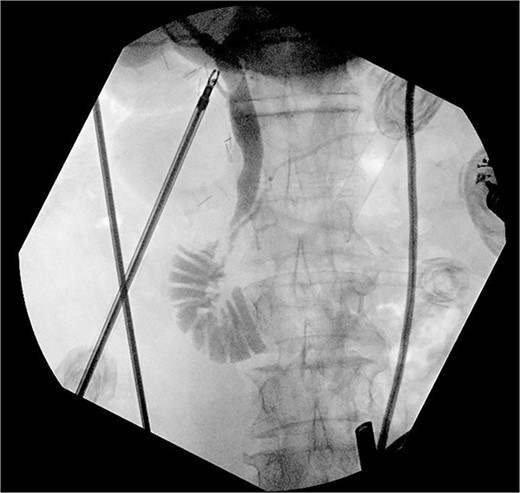

Intraoperative cholangiogram showing pancreaticobiliary malunion with the bile duct entering the main pancreatic duct proximal to the ampulla.